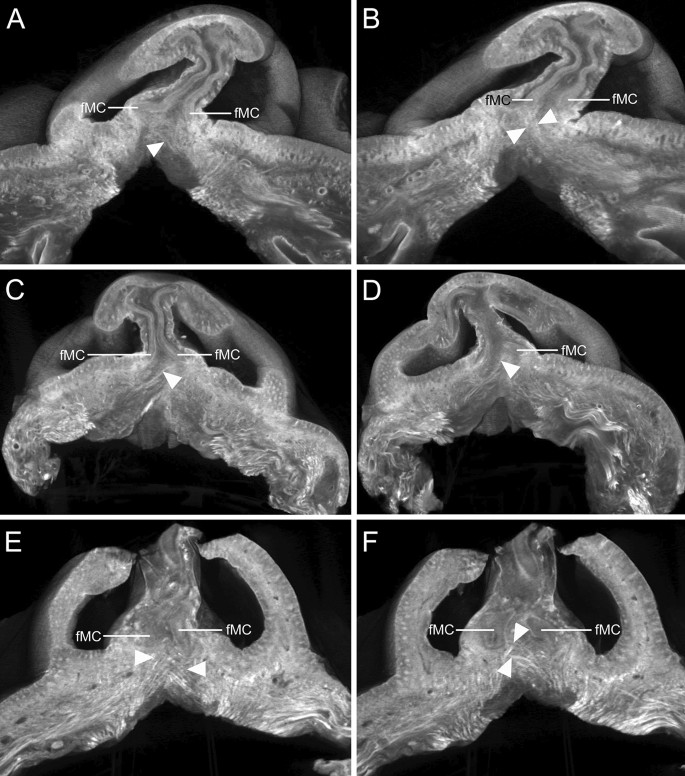

In 28 of 34 cadavers (82.4%), we observed crossing fibers of the DSN or OOr attached to the fMCs, which were bilateral in 11 cadavers (32.4%) and unilateral in 17 (50.0%). The DSN and OOr attached to the fMCs could be categorized into the following six patterns according to presence of the DSN and crossing patterns of the DSN and OOr (Fig. 1):

Type I (n = 6 of 34 cadavers, 17.6%, Fig. 1A), in which the DSN was present bilaterally and both DSNs were predominantly attached to their corresponding fMCs. Some fibers of both DSNs crossed each other to attach contralaterally to the fMCs as bilateral crossing fibers. In two such cadavers, some OOr fibers on one side also crossed the midline to attach to the fMC on the contralateral side with the crossing fibers of the DSN.

Type II (n = 5, 14.7%, Fig. 1B), in which the DSN was present bilaterally and both DSNs were predominantly attached to their corresponding fMCs. Some DSN fibers on one side and some OOr fibers on the contralateral side crossed each other to attach to the fMCs as bilateral crossing fibers.

Type III (n = 10, 29.4%, Fig. 1C), in which the DSN was present bilaterally and both DSNs predominantly attached to their corresponding fMCs. Some DSN fibers on one side crossed to attach to the fMC on the contralateral side as unilateral crossing fibers. In two such cadavers, some OOr fibers crossed together along with the crossing fibers of the DSN or were attached to the corresponding fMC.

Type IV (n = 3, 8.8%, Fig. 1D), in which the DSN was present bilaterally and the DSNs and OOrs had no crossing fibers that attached to the fMCs.

Type V (n = 6, 17.6%, Fig. 1E), in which the DSN was present unilaterally. The DSN on one side and some OOr fibers on the contralateral side were predominantly attached to their corresponding fMCs. Some DSN or OOr fibers on one side crossed to attach to the fMC on the contralateral side as unilateral crossing fibers.

Type VI (n = 4, 11.8%, Fig. 1F), in which the DSN was absent bilaterally. Instead, some OOr fibers beneath the fMCs ascended to attach to the fMCs. In one cadaver, some OOr fibers crossed the midline and were attached to the fMC on the contralateral side.

Crossing patterns of the depressor septi nasi (DSN) and orbicularis oris (OOr) muscles attached to the footplates of the medial crura (fMCs). (A) Type I: Both DSNs (arrowheads) were predominantly attached to the corresponding fMCs, and some of their fibers (arrows) crossed to attach to the fMCs on the contralateral sides as bilateral crossing fibers. (B) Type II: Both DSNs (arrowheads) were predominantly attached to the corresponding fMCs. Some DSN fibers (white arrow) on one side and some OOr fibers (black arrow) on the contralateral side crossed each other to attach to the fMCs as bilateral crossing fibers. (C) Type III: Both DSNs (arrowheads) were predominantly attached to the corresponding fMCs, and some DSN fibers (arrow) on one side crossed to attach to the fMC on the contralateral side as unilateral crossing fibers. Connecting fibers between both DSNs beneath the fMCs were often found in an arched shape in this type. (D) Type IV: The DSNs (arrowheads) were present bilaterally and there were no crossing fibers of the DSN or OOr attached to the fMCs. (E) Type V: The DSN (white arrowheads) on one side and some OOr fibers (black arrowheads) on the contralateral side were predominantly attached to the corresponding fMCs. Some of the DSN (arrows) on one side crossed to attach to the fMC on the contralateral side as unilateral crossing fibers. (F) Type VI: When the DSN was not present, some OOr fibers (arrowheads) ascended to attach to the fMCs instead of the DSNs. DAN depressor alae nasi, SC septal nasal cartilage.